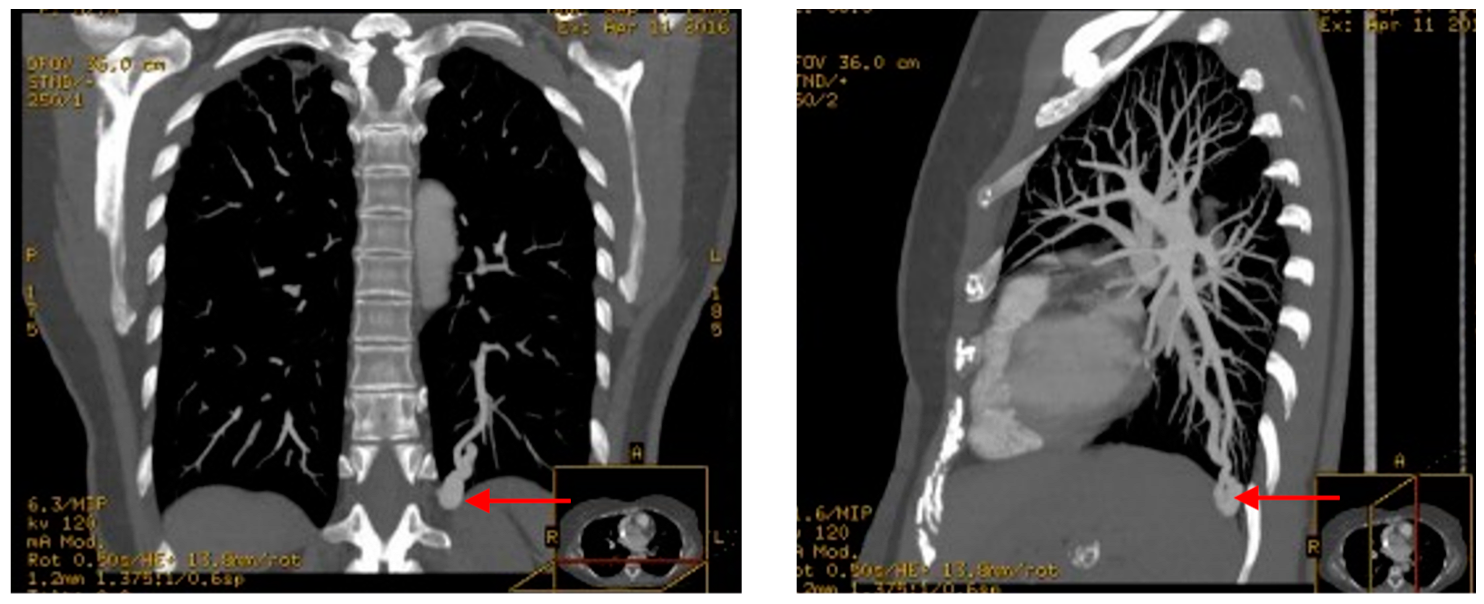

4.1. Pulmonary Arteriovenous Malformations (PAVMs)

| Pulmonary AVMs | 15–50 | Chronic hypoxaemia is only present in case of large pulmonary AVMs. Prevalence 10–20% in HT-II, 60% in HHT-I. |

| Pulmonary AVMs | Transcatheter embolization: Consider in any AVM with afferent vessel >2 mm in diameter. | |

| Chest CT is recommended to identify possible recanalization. | Follow-up with CT scan after embolization every 6 months, then every 3–5 years. | |